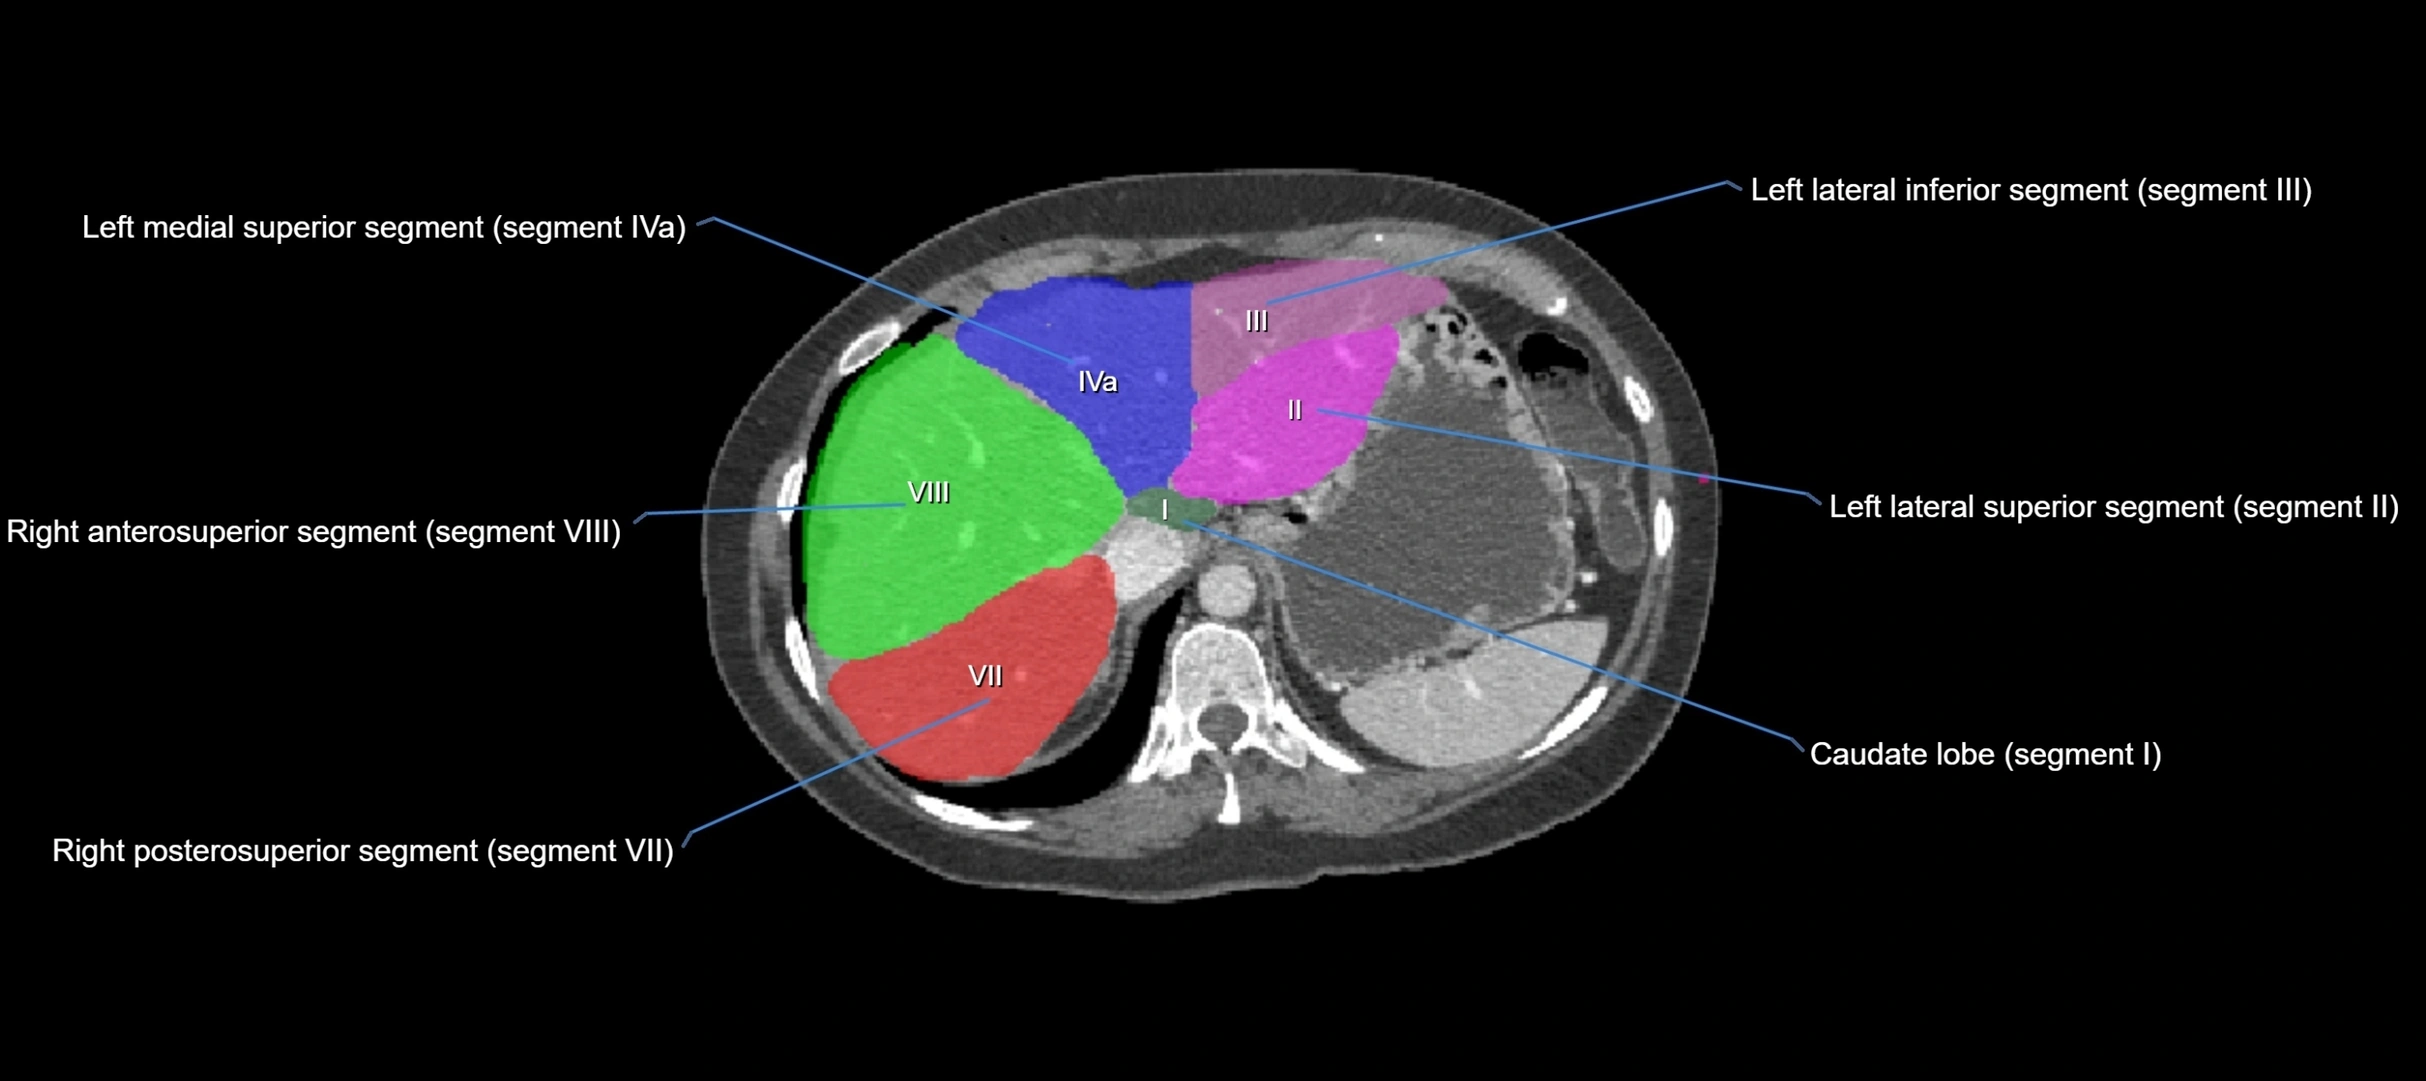

The caudate lobe of the liver is a distinct anatomical subdivision of the liver, designated as segment I in Couinaud’s classification. It lies on the posterior surface of the liver, between the fissure for the ligamentum venosum (left boundary) and the groove for the inferior vena cava (IVC) (right boundary). Superiorly, it is related to the posterior liver surface, and inferiorly it is separated from the left lobe by the porta hepatis.

CT Image

image